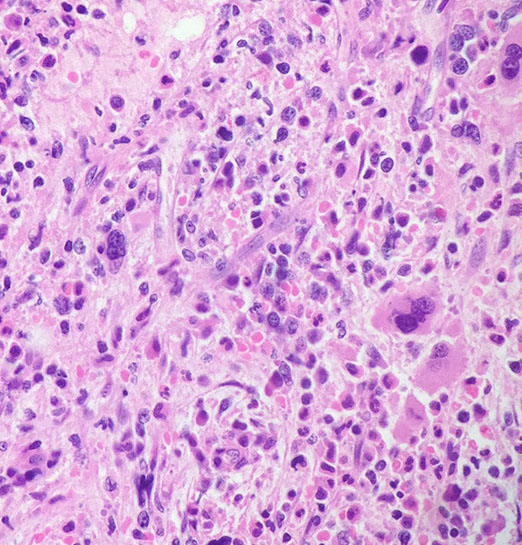

Micro:

- high fatality rate (10%) usually due to fulminant hepatitis or macrophage activation syndrome